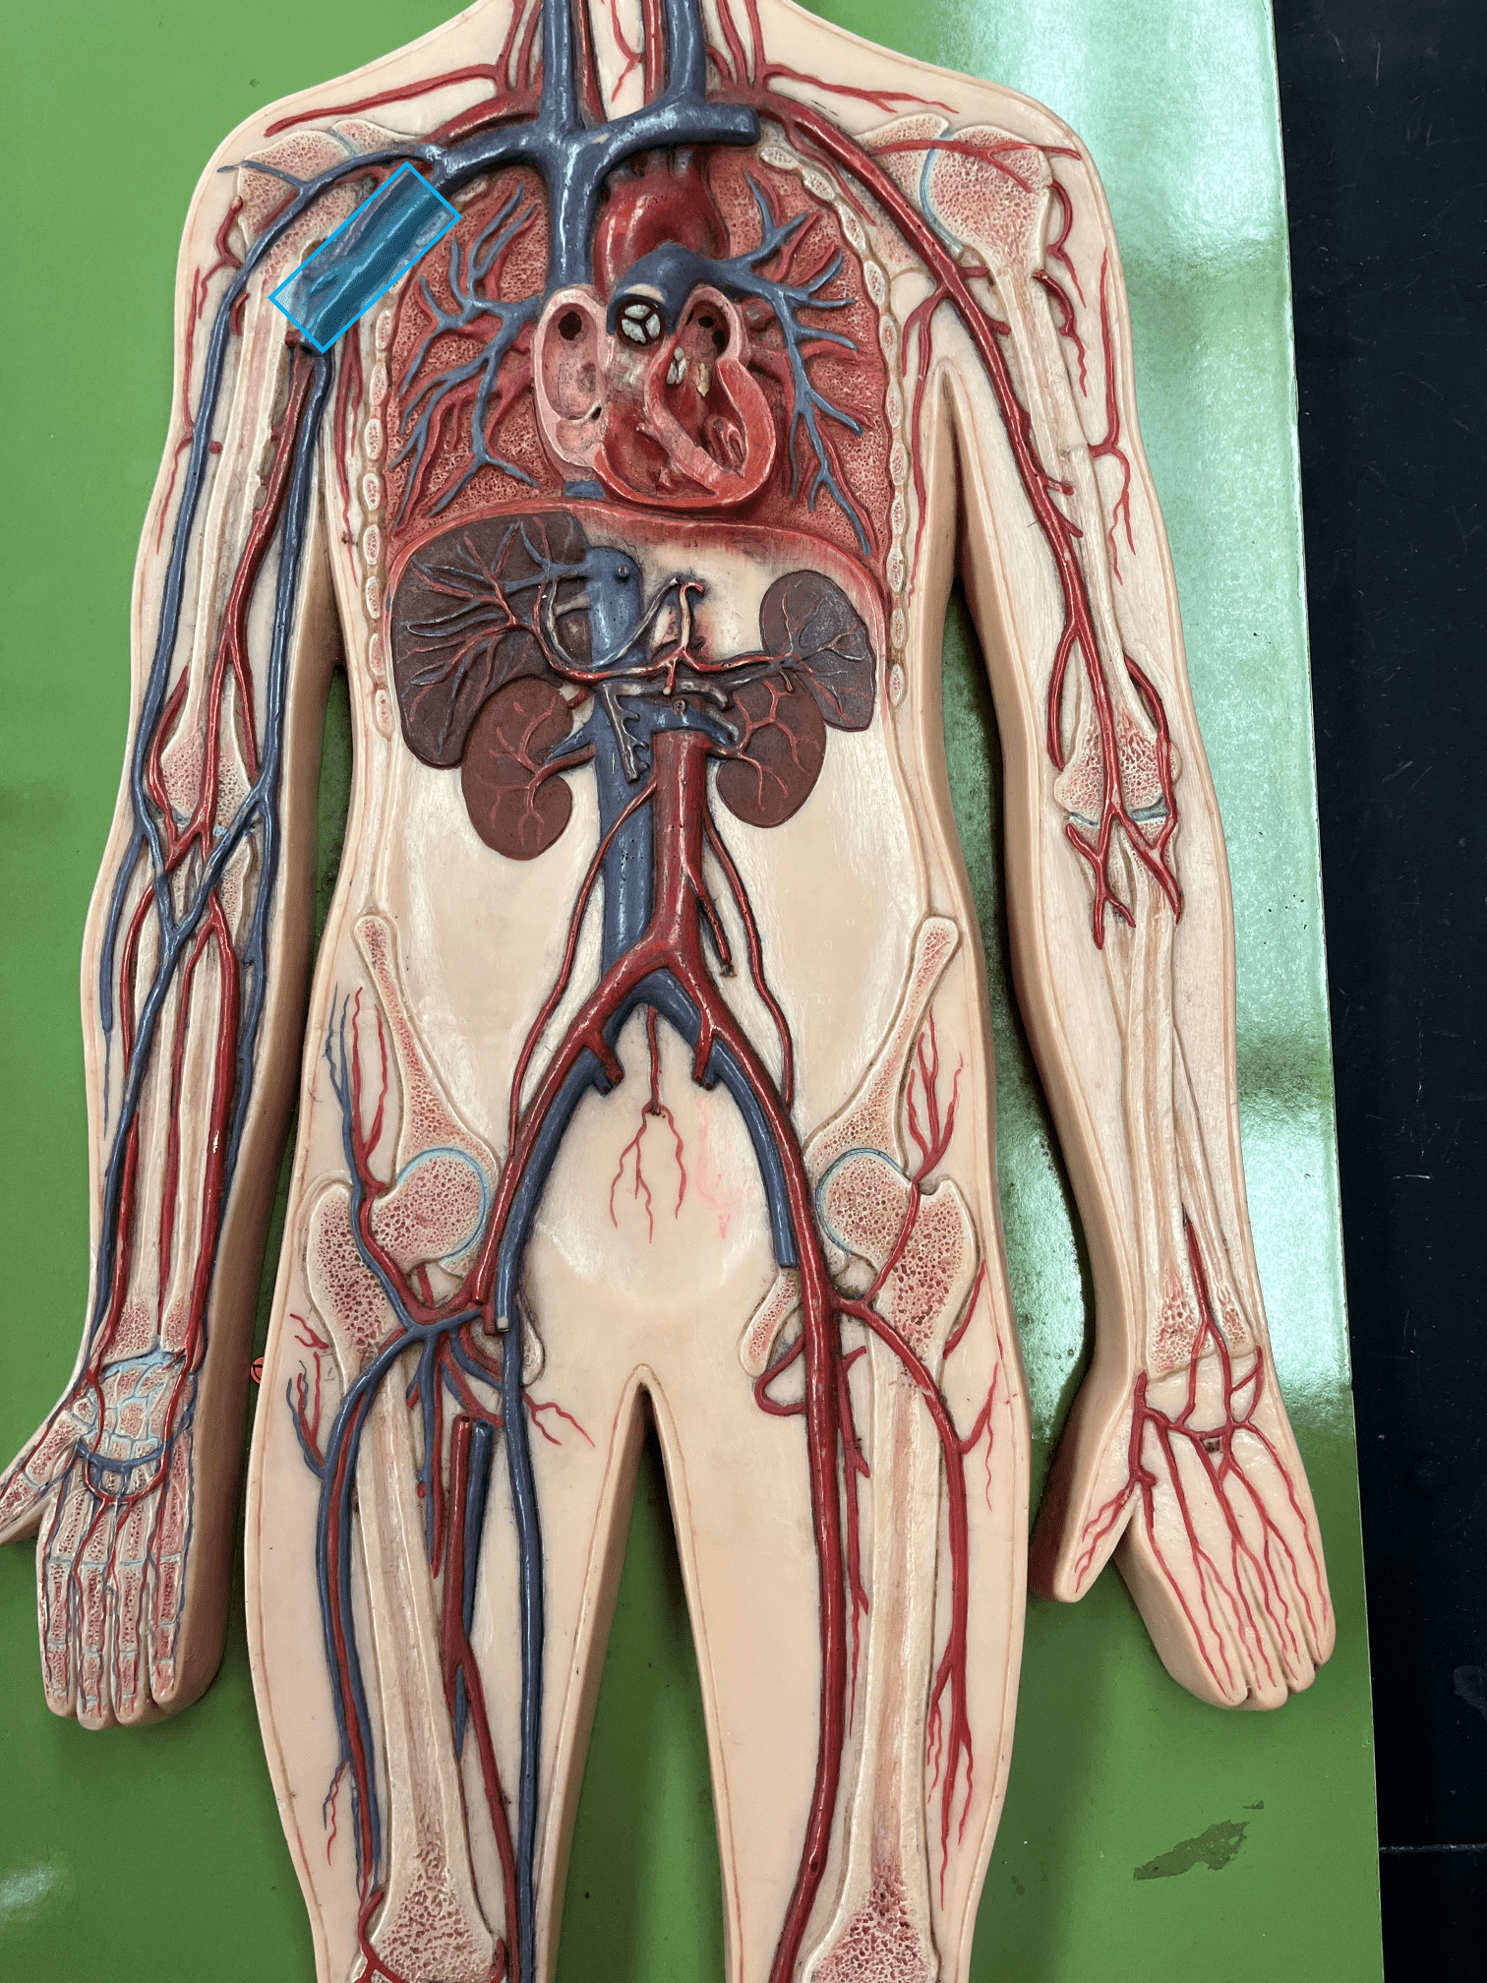

New cards

subclavian vein

brachiocephalic vein